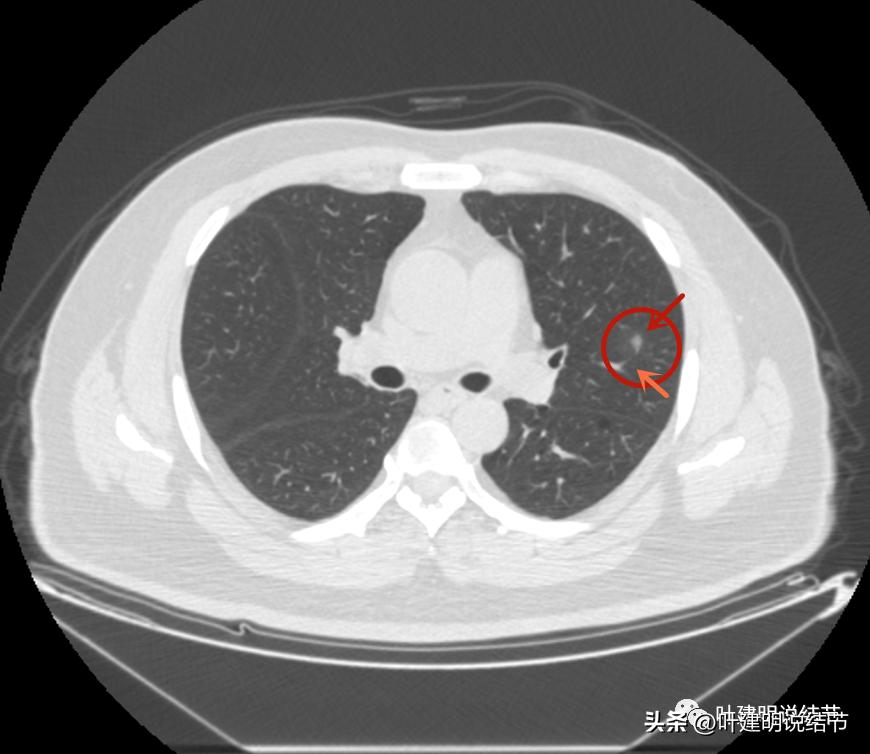

后续再看2022年8月的CT图像,有点惊掉下巴的感觉:

左上叶的病灶1、2、3都没有了!!!完全没有了!那当然说明是炎症性的,居然全部吸收了!

但左上病灶4仍在,形态也没有明显变化,无好转,也无明显进展。这是肿瘤性质的吗?虽然存在2年多了,但因为它的兄弟们都不见了,让我对它认定的肿瘤范畴也产生了怀疑,也许是纤维增生而已呢!

右上叶倒又出现了新的病灶:

右上病灶1:是新出现的,密度甚低,但轮廓较清,不典型增生吗?

右上病灶2:新出现的,整体轮廓较清,但感觉较散在,不致密,也不是圆形或类圆形,大概是炎性的吧!

2020年时同样位置是没有异常的: